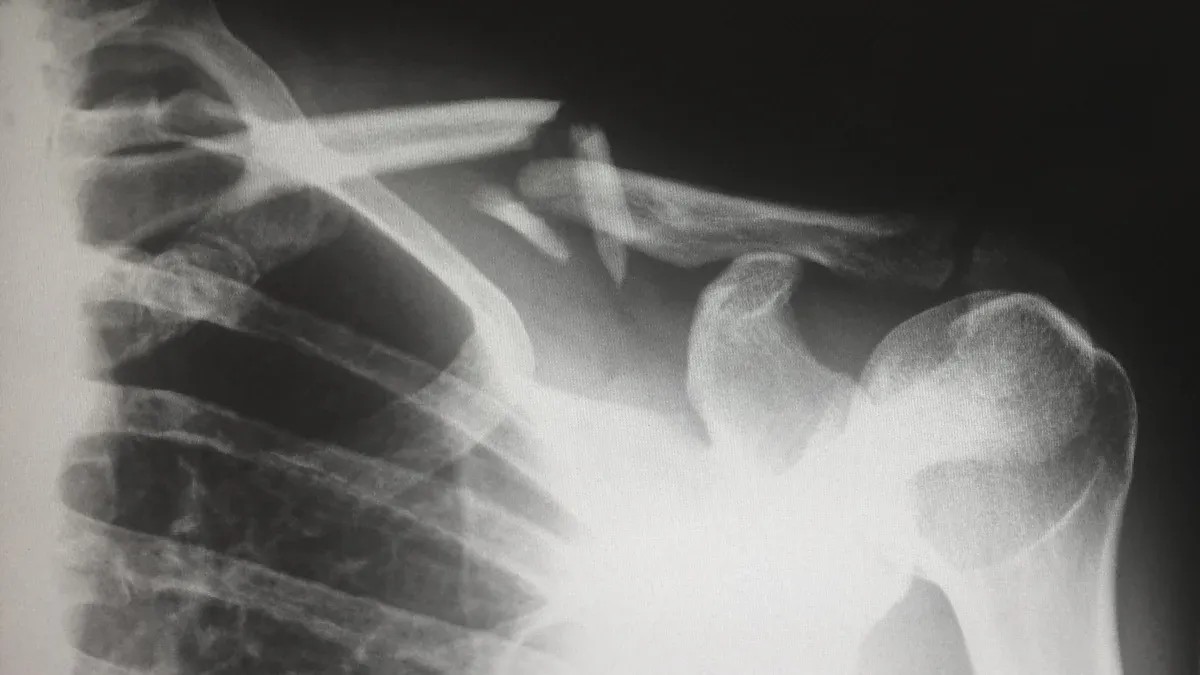

Вы можете услышать, как ваш врач говорит о вывихе сустава переменного тока, когда вы повредите плечо. Эта травма происходит в акромиально-ключичном (AC) суставе, где ключица встречается с самой высокой точкой лопатки. Сустав помогает вашей руке двигаться и сохраняет плечо стабильным.

Каждая десятая травма плеча представляет собой вывих сустава переменного тока.

В общей популяции ежегодно регистрируется от 3 до 4 случаев на 100 000 человек.

Более половины этих травм происходит во время занятий спортом, особенно контактными видами спорта.

Наибольшему риску подвергаются молодые мужчины, особенно в возрасте от 10 до 30 лет. В этой группе почти каждая пятая травма плеча является травмой сустава переменного тока.

Если у вас вывих сустава переменного тока, вы, скорее всего, почувствуете боль, особенно когда вы проводите рукой по груди или поднимаете ее над головой. Связки, которые скрепляют сустав переменного тока, играют большую роль в поддержании устойчивости вашего плеча. Если эти связки повреждаются, плечо может стать нестабильным и болеть.

Вы можете задаться вопросом, когда хирургическое вмешательство станет лучшим выбором при вывихе переменного сустава. Врачи используют классификацию Роквуда, чтобы решить, нужна ли вам операция. Эта система сортирует травмы по тому, насколько сильно сместился сустав и насколько нестабильно чувствует себя плечо.